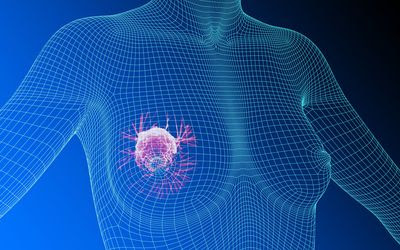

कैंसू डार्लिंग! किस्सू डियर!!

मेरा ना…….म है – कैंसर!

प्यार से लोग मुझे कुछ भी नहीं कहते.

न कैंसू, न किस्सू, न कैन्स.

कैंसर!

मुझे पता है तेरा नाम

दी है अपने ही घर के तीन लोगों की आहुति

फिर भी नहीं भरा तुम्हारा पेट जो

आ गए मेरे पास?

और अब गा रहे हो बड़ा चमक-छमक के, कि

मेरा ना……म है कैंसर!

और कर भी रहे हो शिकायत कि

नहीं लोग पुकारते हैं तुम्हें प्यार से

किस्सू डियर या कैंसू डार्लिंग!

आओ,

अब, जब तुम आ ही गए हो मेरे सीने में

मेरे दिल के ठीक ऊपर

जमा ही लिया है डेरा

तो कह रही हूँ तुम्हें

कैंसू डार्लिंग, किस्सू डियर!

खुश!

लो, पूरी करो अपनी मियाद

और चलते बनो

अपने देस-नगर को,

जहां से मत देना आवाज किसी को

न पुकारना किसी का नाम

इठलाकर, बल खाकर

ओ माई कैंसू डियर!

ओ माई किस्सू डार्लिंग!!